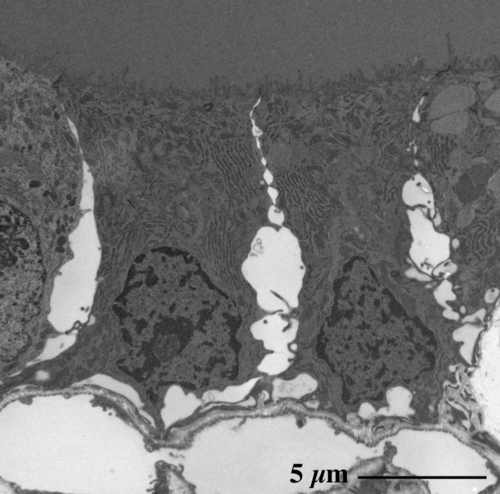

ラット甲状腺にみられる濾胞 follicle と内部のコロイド物質

(エポン樹脂包埋準超薄切片のトルイジンブルー染色光顕像)

濾胞上皮細胞 follicle epithelial cells